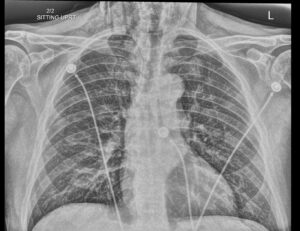

Dental Free Air CXR 2 Inverted Unannotated. JETem 2025